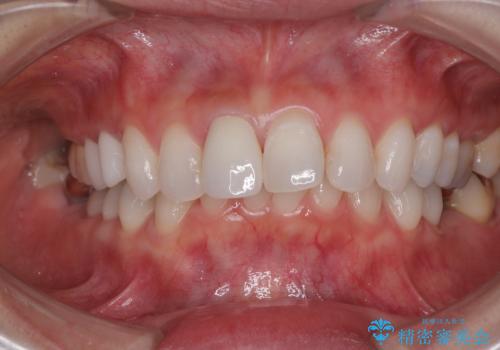

- 前歯の変色と、以前装着したクラウンが黄ばんできたことを気にして来院された患者様です。

前歯に変色が起こる場合、神経組織の失活により引き起こる可能性が高いため、診察を行ったところ、根尖部の病変や叩いたときの痛みなどが認められました。

まずは根管治療を行い、痛みの消退を確認してからオールセラミッククラウンによる補綴治療を行うこととしました。

黄ばんできてしまった小臼歯部のクラウンは、根尖部に症状を認めないため、そのままオールセラミッククラウンによる補綴治療を行うこととしました。

色がやや白いと感じましたが、ご自身でホームホワイトニングをされているそうで、今後周辺の歯を白くしていくとのことでした。

前歯に痛みがあるという実感はなかったそうですが、診察で叩いたときの痛みを感じた際、今までに同様の痛みや違和感を感じたことがあったとのことでした。

初回の根管治療で痛みや違和感は消退したため、その後は速やかに補綴治療を行いました。